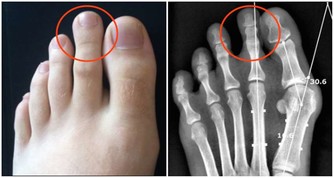

這種從肛門排出的廢氣,有時會帶有臭味;這是因為排氣時人體會釋放少量氫化硫,而這種物質具有防止細胞受損的作用,甚至可以預防心血管疾病和中風。